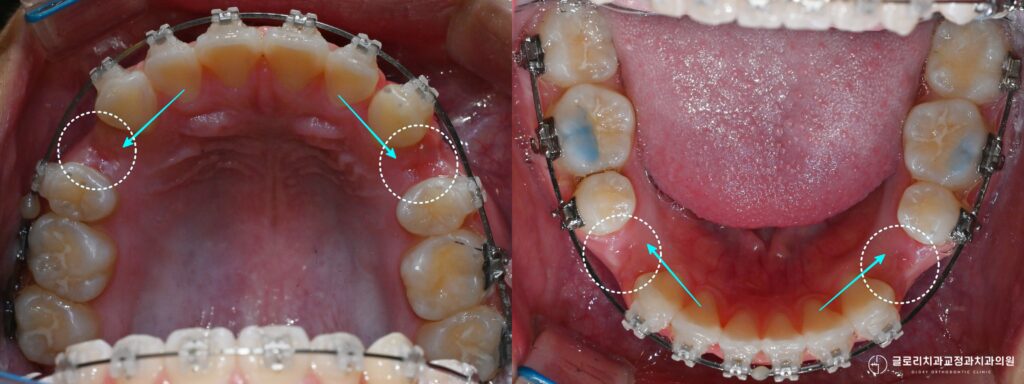

사진에서 보이는 것처럼 발치 후 생긴 공간은 돌출된 앞니를 후방 이동시키는 데 사용되며 동시에 매복된 송곳니가 나올 자리를 마련하는 역할도 하게 됩니다.

한 번의 치료 과정에서 두 가지 목표를 함께 달성할 수 있는 것입니다.

공간이 충분히 확보되었다면 매복된 송곳니가 스스로 내려오는지 일정 기간 관찰하는 단계를 거칩니다.

주변에 방해 요소가 없어지면 자연스럽게 맹출되는 경우도 있기 때문입니다.

(그러나 공간이 마련되었음에도 송곳니가 움직이지 않는 경우라면 외과적 노출술이 필요할 수 있습니다.)

다만 견인에 소요되는 기간은 매복 깊이와 각도에 따라 달라질 수 있어 전체 치료 기간에 영향을 미치게 됩니다.